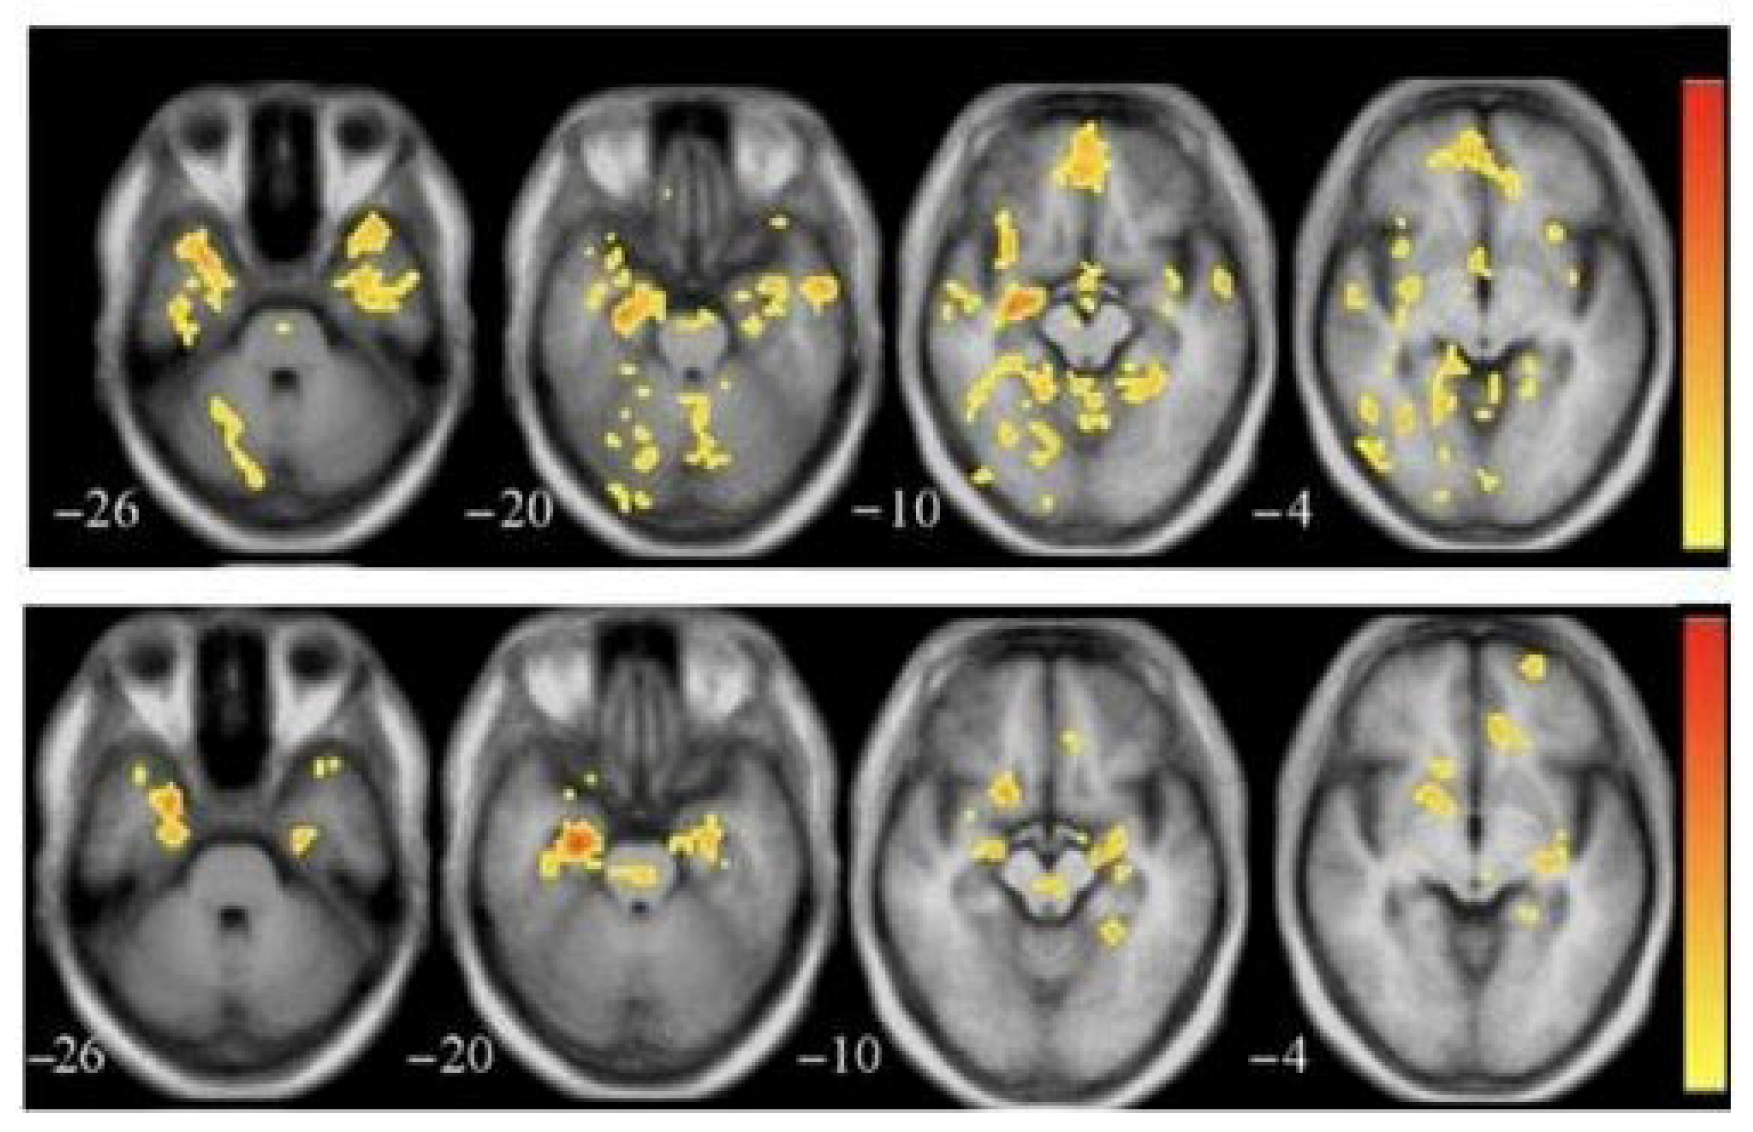

3.2. Functional Magnetic Resonance Imaging (fMRI)